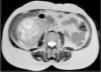

Renal ultrasound showed a well-defined mass in the lower pole of the right kidney. Renal magnetic resonance imaging was performed to clarify its nature and relations, which showed a well-defined, macronodular mass measuring 85mm at its widest point, with radial expression and a central necrotic scar with high contrast uptake, suggestive of renal oncocytoma (Figs. 1 and 2).

Total right nephrectomy was subsequently performed and the surgical specimen was sent for pathoanatomical and immunohistochemical study. This confirmed a solid tumor measuring 85×70×65mm, consisting of granular and eosinophilic cytoplasm, positive for Cam 5.2 and negative for CD10, and focally positive for CK7 and vimentin, compatible with a diagnosis of renal oncocytoma.